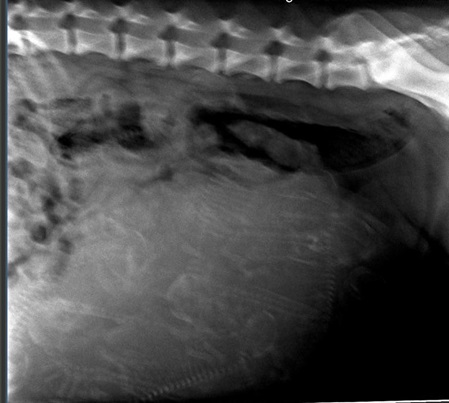

Röntgen

Hier kann man das Wunder sehen...